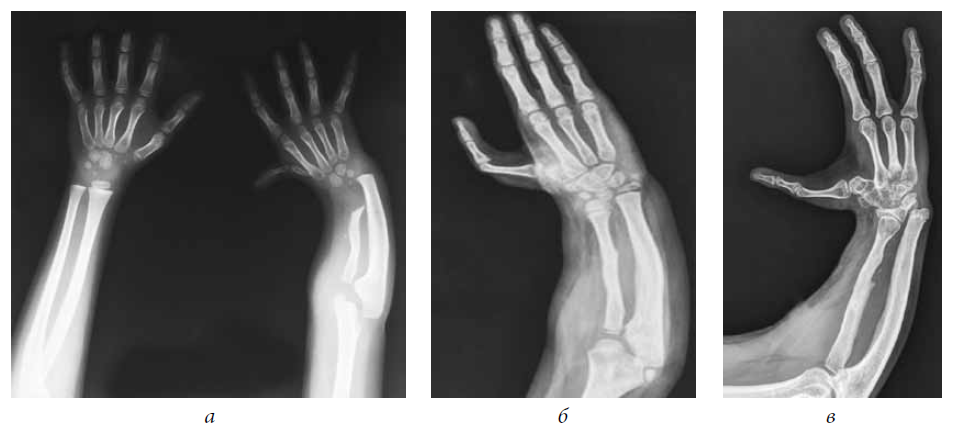

Patient D., 6 years old, had congenital right-sided radial clubhand, hypoplasia of the first finger. For up to 3 years, the patient received conservative treatment (plastering, physiotherapy). At the age of 3 years, compression-distraction apparatus was installed to bring the hand to the middle position. A year later there was a relapse of the hand deviation. During the clinical examination, forearm shortening by 7 cm was noted, and radial deviation of the hand to 32° was registered; it was impossible to passively bring the hand to the middle position, and there was hypoplasia of the first ray (Fig. 1 a). It was decided to restore the radial bone by microsurgical autografting of the vascularized epimetaphys of the second metatarsal bone, including the epiphysial plate. The postoperative period included no abnormalities. Intramedullary wires on the forearm and foot were removed 6 weeks postoperatively.

Fig. 1. Radiograph of the upper limb in patient D. (a) Before the surgical treatment, (b) 3 years and (c) 8 years after microsurgical autografting of the vascularized epimetaphys of the second metatarsal bone, including the epiphysial plate

On examination 3 years (Fig. 1 b) and 8 years (Fig. 1 c) postoperatively, the hand was in the middle position, and mild shortening of the radial bone was observed radiographically.